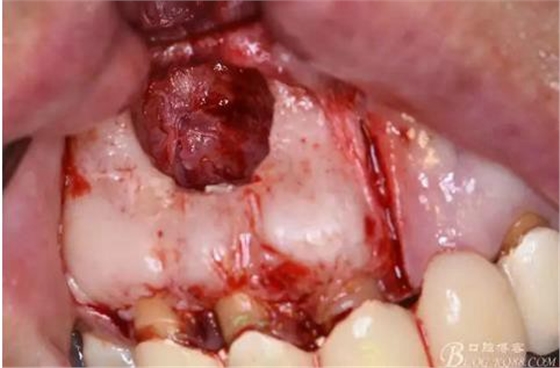

圖21.摘除的12囊壁